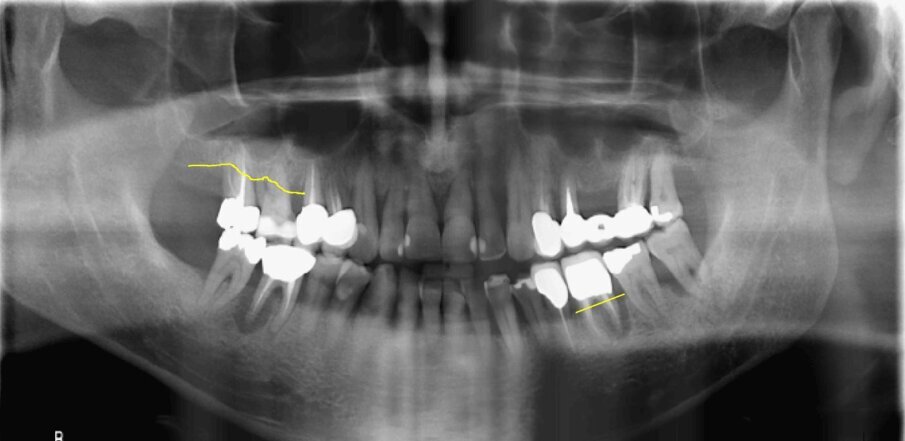

I pazienti considerati eleggibili all’inclusione erano coloro che fossero stati sottoposti a riabilitazione con protesi full-arch a carico immediato con tecnica Flat-one-Bridge (Figg. 1, 2). I pazienti, già al tempo della chirurgia, erano inclusi solo se maggiorenni, complessivamente in salute, condiscendenti alle misure di igiene orale prescritte e alle visite di controllo programmate. I criteri di esclusione erano: presenza di fattori sistemici o locali che avrebbero potuto controindicare la chirurgia, scarsa igiene orale, abitudine al fumo di più di 10 sigarette al giorno, gravidanza, storia di dipendenza e/o abuso di sostanze stupefacenti e/o alcool.

Fig. 2_Radiografia panoramica pre-operatoria di uno dei pazienti inclusi al tempo della chirurgia.